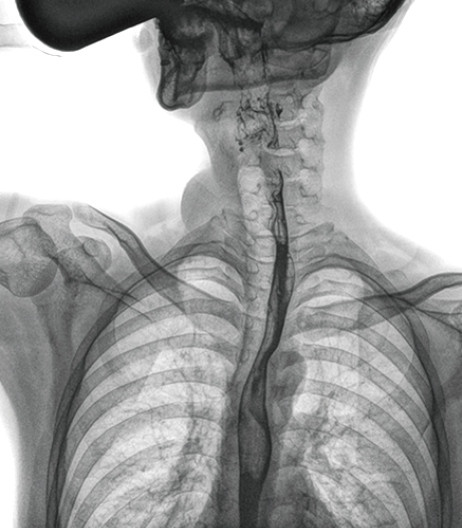

食管造影是食管病變的基本檢查方法,可以發現食管癌的特征性改變——食管粘膜的中斷和破壞,病人常感覺吞咽障礙,此特征在臨床中最常見,也是早期食管癌的典型表現。一般伴隨的特征有管壁充盈缺損、龕影、軟組織塊影、食管腔狹窄等;在透視下還可看到食管壁僵硬、蠕動緩慢等。

動態DR能夠實現大幅面透視,瞬時高清點片等。在食管造影檢查中,由于吞咽鋇劑后,造影劑流速非???,在一個大幅面上方便觀察食管的病變。瞬時點片,可以實時捕捉到病變部位的影像,從而可以快速做出診斷。普利德多功能動態DR擁有17×17英寸超大視野,一次曝光即可顯示整個食管,更方便觀察食管的病變,確定病變的范圍,對診斷和治療有重要參考價值。

動態DR可以動態觀察管壁蠕動是否僵硬,以鑒別良、惡性狹窄,不但在透視過程中,可實時高清點片,實現毫秒級動靜態圖像切換,快速捕捉病變部位的影像,成像清晰而迅速,盡可能減少食管功能性障礙患者因吞咽困難而忍受痛苦的時間,同時提高醫生做出正確診斷的效率,還能實時保存視頻影像,反復觀察、分析,明確病變范圍,對手術有重要的指導意義。

與過去的數字胃腸機比較,動態DR圖像分辨率高,對食管的全景觀察,局部粘膜破壞、中斷,管腔狹窄以及病灶范圍的顯示清晰度明顯更優。

上消化道造影高清圖像

由此不難看出,動態DR在食管造影的臨床應用上,相比于其他檢查手段,成像清晰、應用便捷,而且能夠充分顯示食管的局部和整體結構形態,并以此揭示相關形態和功能性改變,更有利于助力實現精準診斷。